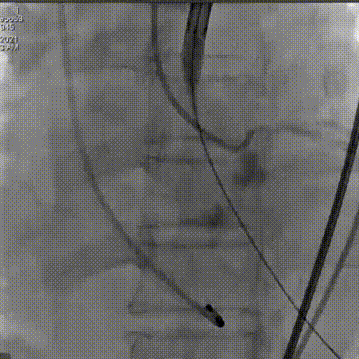

主动脉根部造影可见重度钙化

22mm球囊预扩